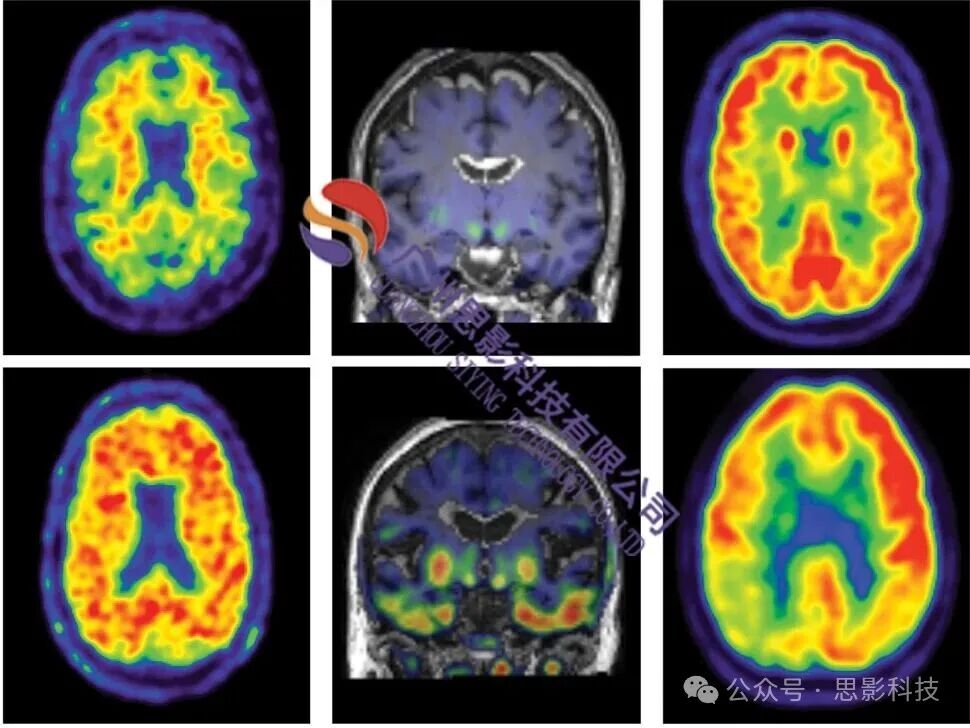

已有的研究成果表明,PET图像分析在揭示脑代谢活动和脑疾病机制方面具有不可替代的价值。通过检测放射性示踪剂在脑内的分布,PET技术能够精准反映脑区的代谢水平、血流变化以及神经递质活动,为研究者提供高灵敏度、高特异性的功能信息。例如,基于体素的SUVR分析可以识别出与神经退行性疾病(如阿尔茨海默病、帕金森病)相关的代谢异常区域,结合图论指标计算,为研究者提供了从局部到全局的脑功能网络视角,进一步深化了对脑疾病机制的理解。

然而,PET图像分析涉及复杂的预处理流程和多样化的分析方法,许多研究者在实际操作中面临技术门槛高、软件工具复杂等挑战。针对这一需求,思影科技特别推出PET图像分析专题班,课程内容涵盖从基础到高级的全流程实操,包括PET数据处理原理、基于SPM的预处理与统计分析、基于体素和表面的SUVR分析、PET连接矩阵构建及图论指标计算、基于个体相似度的PET脑网络分析等。通过六天的学习,学员将掌握PET图像分析的核心技术,并能够独立完成从数据预处理到结果可视化的全流程分析。如果您需要其他模态脑影像分析课程和服务,请浏览以下链接(直接点击即可浏览),感谢转发支持。(可添加微信号19962074063或18983979082咨询):

内容主要包括:PET分析原理、PET处理流程、基于体素的SUVR分析、基于表面的SUVR分析、基于感兴趣区的SUVR分析、Centiloid计算、PET脑网络构建、基于个体相似度的PET脑网络分析、图论指标计算和统计。